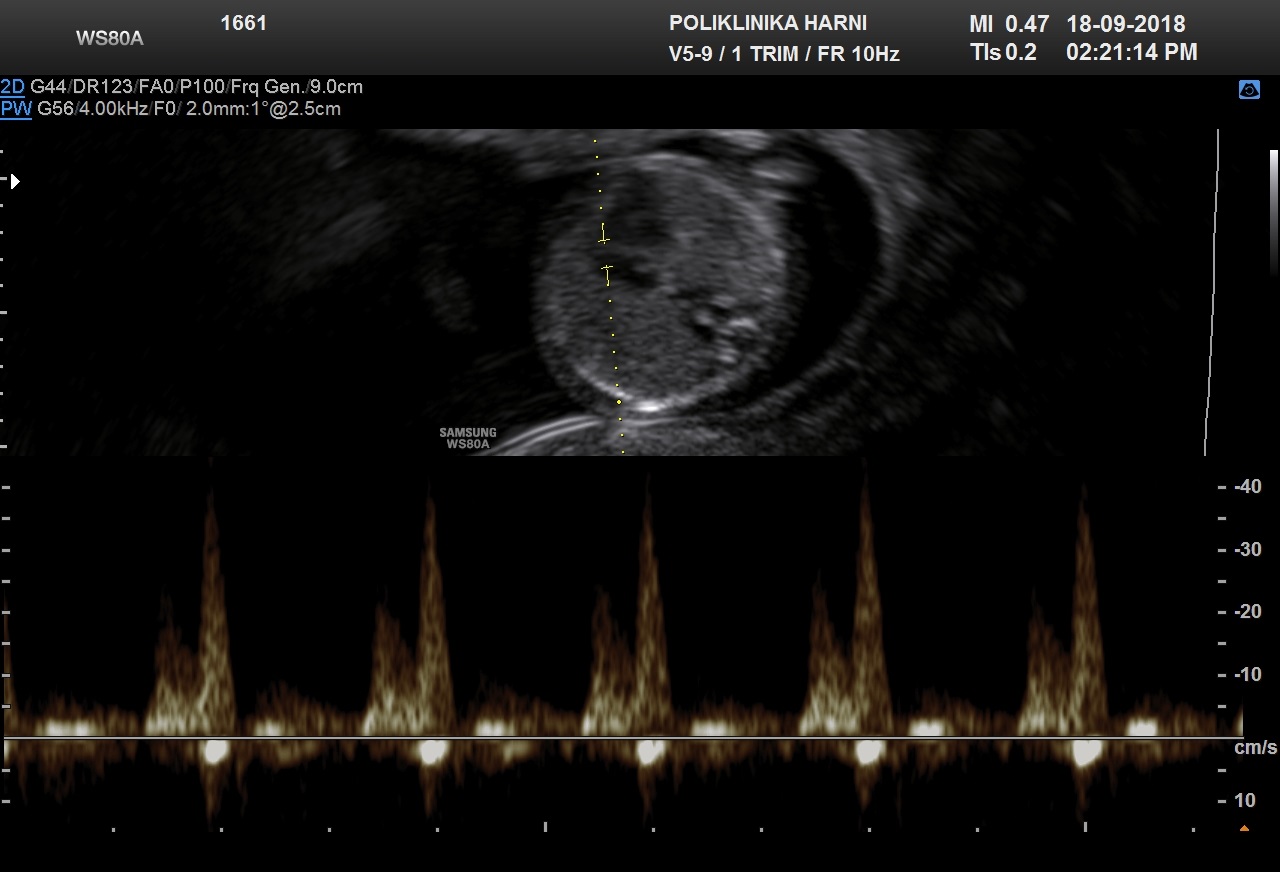

Trikuspidna regurgitacija

U procjeni protoka kroz trikuspidalno ušće važno je da se poštuju sljedeći kriteriji:

- Gestacija bi trebala biti 11 + 0 do 13 + 6 tjedana, a CRL 45-84 mm.

- Fetus se ne smije pomicati.

- Povećanje slike treba biti takvo da prsni koš fetusa zauzima cijeli zaslon.

- Treba dobiti apikalni prikaz četiri komore fetalnog srca.

- Color doppler se ne smije koristiti jer je nepouzdan za dijagnozu trikuspidalne regurgitacije u prvom tromjesečju.

- Pulsni dopplerski gate treba biti velik (2 do 3 mm) i postavljen na trikuspidalno ušće.

- Kut insonacije u smjeru protoka bi trebao biti manji od 30 stupnjeva od smjera interventrikularnog septuma.

- Trikuspidalno ušće može biti insuficijentno u jednom ili više od tri njegova zalistka i zato bi se kaliper trebao postaviti preko ušća najmanje tri puta, u pokušaju da se ispita čitavo ušće.

- Sweep speed treba biti veliki (2 do 3 cm / s) tako da se valni oblici široko šire za bolju procjenu.

Normalan i nenormalan protok

Normalni profil bez regurgitacije tijekom sistole.

Regurgitacija tijekom otprilike polovine sistole i brzine veće od 60 cm / s.

Pogreške kod trikuspidne regurgitacije:

- Mlaz proizveden aortnim ili plućnim arterijskim protokom krvi, koji u ovom stadiju gestacije može proizvesti maksimalnu brzinu od 50 cm / s.

- Kratki obrnuti "šiljak" nastao zatvaranjem zaliska ušća.

Trikuspidalna regurgitacija

S 11-13 tjedana trikuspidalna regurgitacija pronađena je u otprilike:

- euploidnih fetusa 1%

- fetusa s trisomijom 21 55%

- fetusa s trisomijom 18 30%

- fetusa s trisomijom 13 30%

Trikuspidalna regurgitacija češća je ako je gestacija manja 11 nego 13 tjedana i ako je NT veći.

Procjena trikuspidalne regurgitacije poboljšava učinkovitost kombiniranog probira povećavajući stopu otkrivanja s 90% na 95% i smanjujući lažno pozitivnu stopu s 3% na 2,5%.